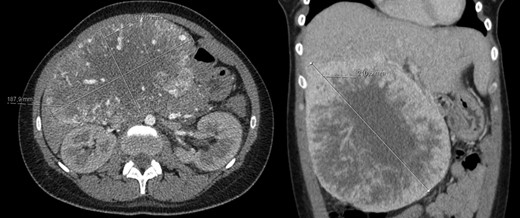

At 16 months, follow-up, local recurrence was identified on CT scan, showing an expansive heterogeneous lesion, below the stomach, with 7.4 cm of maximum diameter, showing no cleavage plan with the stomach (Fig. 4).

AP-CT – expansive heterogeneous lesion, with 7.4 cm, showing no cleavage plan with the stomach.